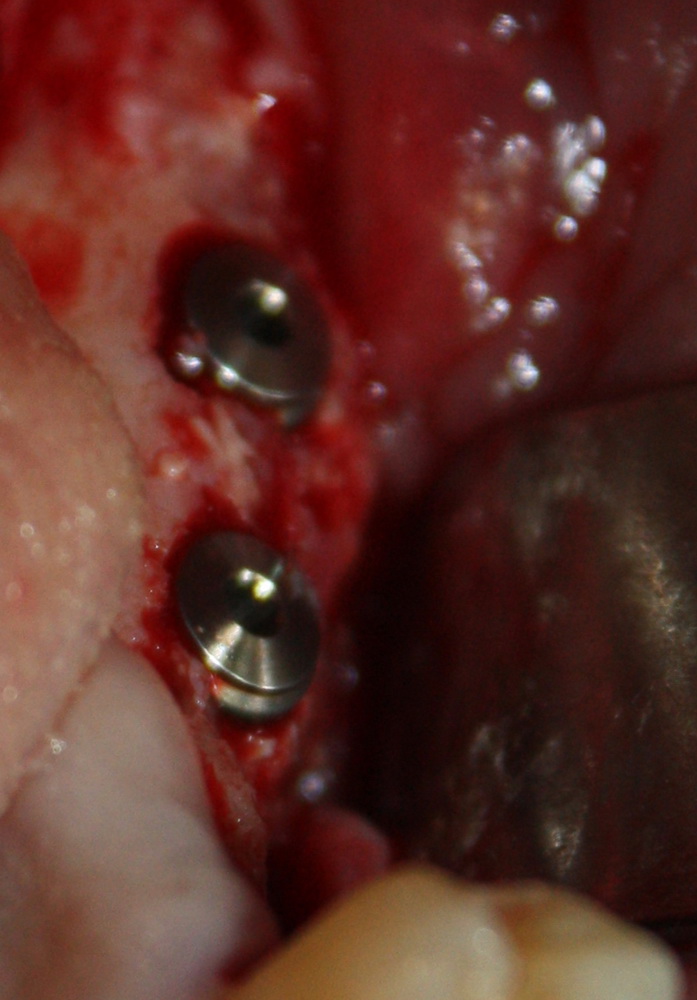

с трудом выковыриваем сетку и ищем имплантат:

чтобы поставить формирователь: